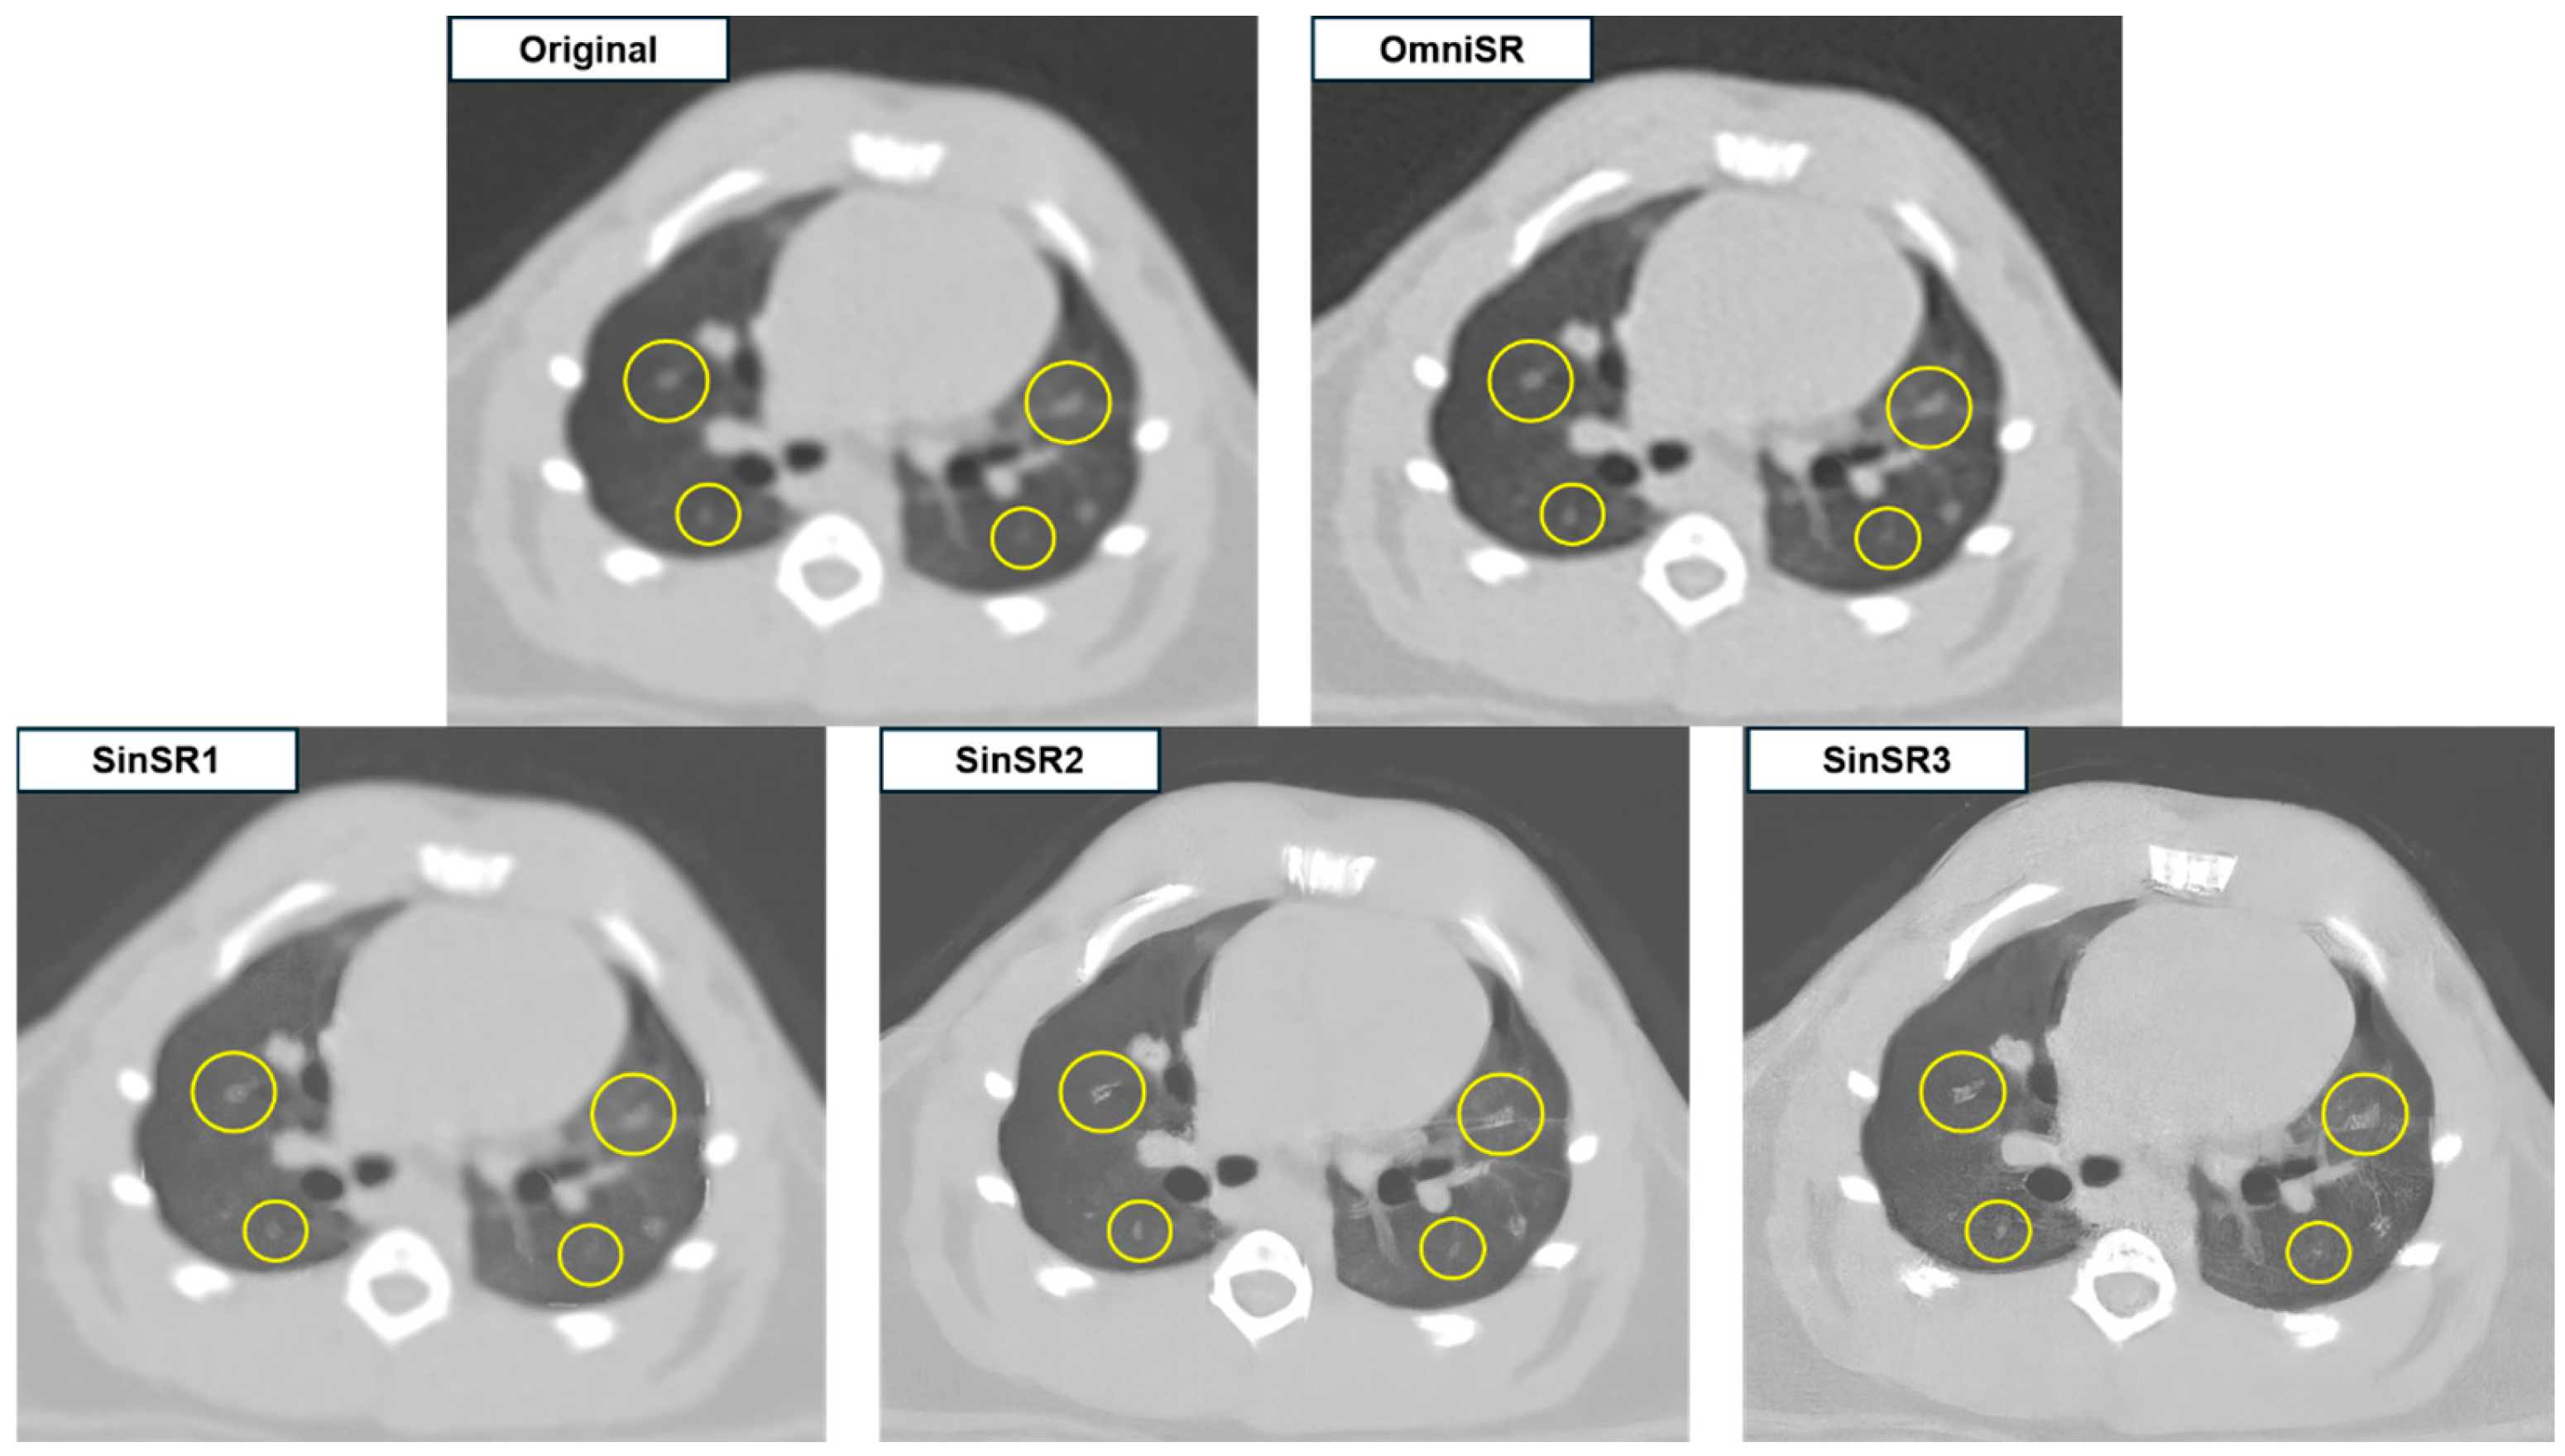

| Margin of lesions | R1 | 4.07 ± 0.73 | 1.09 ± 0.32 | 1.10 ± 0.33 | 1.81 ± 0.90 | N/A |

| R2 | 3.88 ± 0.76 | 1.09 ± 0.32 | 1.10 ± 0.33 | 1.75 ± 0.82 | N/A | |

| Mean | 3.97 ± 0.75 | 1.09 ± 0.32 * | 1.10 ± 0.33 *† | 1.78 ± 0.86 *§ | <0.001 | |

| Nodule/mass detectability | R1 | 4.51 ± 0.85 | 1.25 ± 0.66 | 1.25 ± 0.66 | 1.50 ± 0.70 | N/A |

| R2 | 4.40 ± 0.83 | 1.15 ± 0.52 | 1.16 ± 0.53 | 1.67 ± 0.81 | N/A | |

| Mean | 4.46 ± 0.84 | 1.20 ± 0.59 * | 1.20 ± 0.60 *† | 1.58 ± 0.76 *§ | <0.001 | |

| Anatomic structure similarity | R1 | 3.00 ± 0.00 | 1.00 ± 0.00 | 1.00 ± 0.00 | 2.06 ± 0.91 | N/A |

| R2 | 3.00 ± 0.00 | 1.00 ± 0.00 | 1.00 ± 0.00 | 2.20 ± 0.90 | N/A | |

| Mean | 3.00 ± 0.00 | 1.00 ± 0.00 * | 1.00 ± 0.00 *† | 2.13 ± 0.90 *§ | <0.001 | |

| Image noise | R1 | 3.00 ± 0.00 | 3.55 ± 0.50 | 3.55 ± 0.50 | 4.00 ± 0.00 | N/A |

| R2 | 3.00 ± 0.00 | 3.51 ± 0.50 | 3.48 ± 0.50 | 3.80 ± 0.40 | N/A | |

| Mean | 3.00 ± 0.00 | 3.53 ± 0.50 * | 3.51 ± 0.50 *† | 3.90 ± 0.30 *§ | <0.001 | |

| Image artifact | R1 | 3.00 ± 0.00 | 1.67 ± 0.47 | 1.49 ± 0.50 | 1.69 ± 0.47 | N/A |

| R2 | 2.94 ± 0.24 | 1.65 ± 0.48 | 1.53 ± 0.50 | 1.72 ± 0.45 | N/A | |

| Mean | 2.97 ± 0.17 | 1.66 ± 0.48 * | 1.51 ± 0.50 *† | 1.71 ± 0.46 *†§ | <0.001 | |

| Overall image quality | R1 | 4.78 ± 0.42 | 1.66 ± 0.74 | 1.77 ± 0.71 | 3.14 ± 0.79 | N/A |

| R2 | 4.71 ± 0.48 | 1.65 ± 0.73 | 1.76 ± 0.70 | 3.08 ± 0.77 | N/A | |

| Mean | 4.75 ± 0.45 | 1.66 ± 0.73 * | 1.77 ± 0.70 *† | 3.11 ± 0.78 *§ | <0.001 |